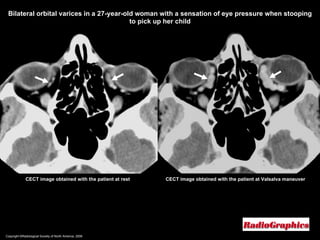

Copyright ©Radiological Society of North America, 2008 CECT image obtained with the patient at rest Bilateral orbital varices in a 27-year-old woman with a sensation of eye pressure when stooping to pick up her child CECT image obtained with the patient at Valsalva maneuver